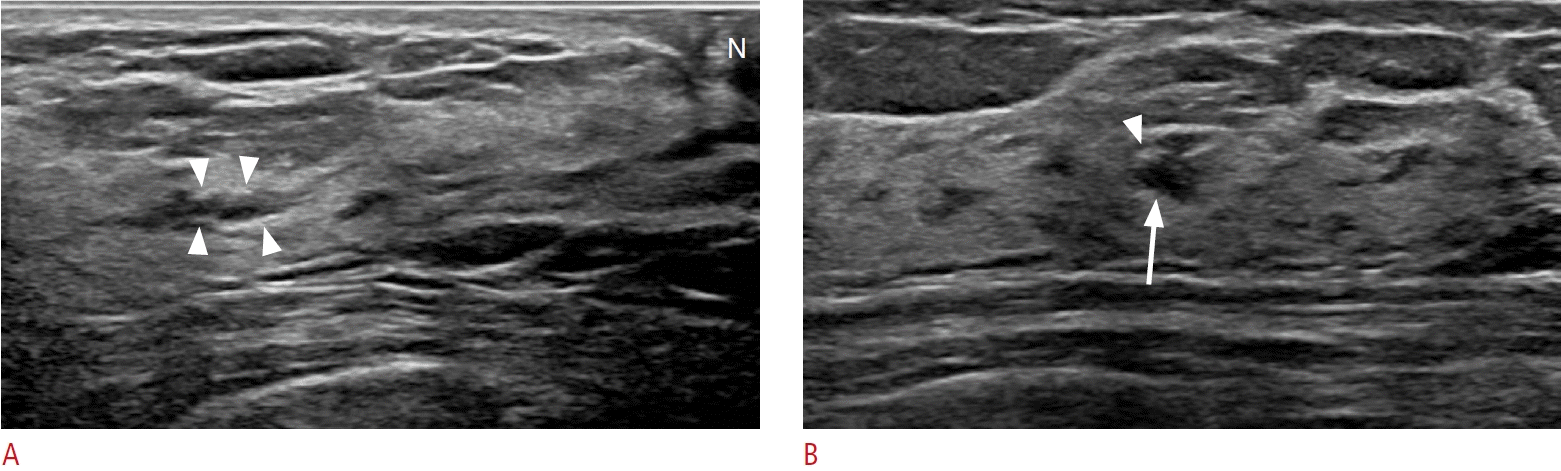

21. Lee SJ, Sobel LD, Shamis M, Mahoney MC. Asymmetric ductal ectasia: an often overlooked sign of malignancy. AJR Am J Roentgenol. 2019; 213:473–481.